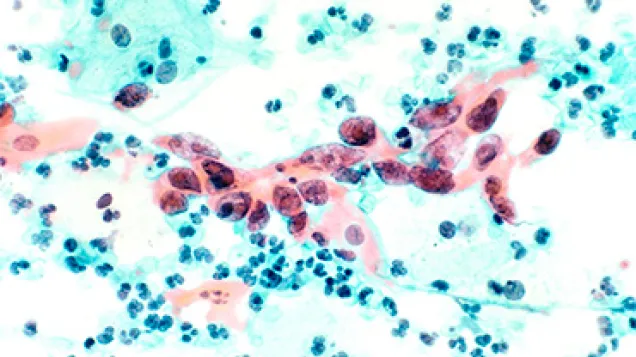

HPV vaccine: don't get misguided - check the FACTS!